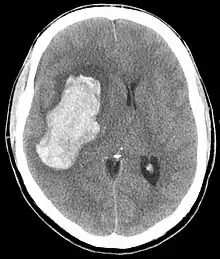

| CT scan depicting intracranial hemorrhage, a possible complication of hypertensive emergency. Patients with spontaneous intracranial hemorrhage present with newfound headache and neurologic deficits. | |

- Abnormal sensations

In the brain, hypertensive encephalopathy - characterized by hypertension, altered mental status, and swelling of the optic disc - is a manifestation of the dysfunction of cerebral autoregulation. Cerebral autoregulation is the ability of the blood vessels in the brain to maintain a constant blood flow. People with chronic hypertension can tolerate higher arterial pressure before their autoregulation system is disrupted. Hypertensives also have an increased cerebrovascular resistance which puts them at greater risk of developing cerebral ischemia if the blood flow decreases into a normotensive range. On the other hand, sudden or rapid rises in blood pressure may cause hyperperfusion and increased cerebral blood flow, causing increased intracranial pressure and cerebral edema, with increased risk of intracranial bleeding.[7]

Consequences of hypertensive emergency result after prolonged elevations in blood pressure and associated end-organ dysfunction. Acute end-organ damage may occur, affecting the neurological, cardiovascular, kidney, or other organ systems. Some examples of neurological damage include hypertensive encephalopathy, cerebral vascular accident/cerebral infarction, subarachnoid hemorrhage, and intracranial bleeding. Cardiovascular system damage can include myocardial ischemia/infarction, acute left ventricular dysfunction, acute pulmonary edema, and aortic dissection. Other end-organ damage can include acute kidney failure or insufficiency, retinopathy, eclampsia, lung cancer, brain cancer, leukemia and microangiopathic hemolytic anemia.